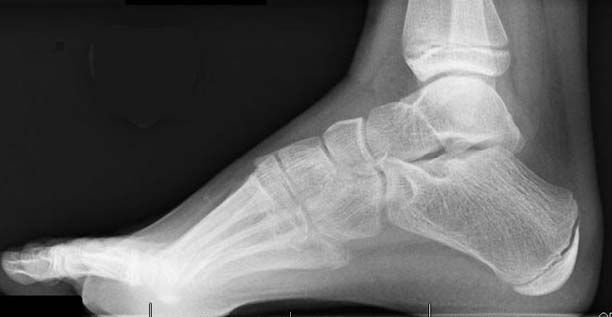

- X-rays. X-rays provide clear images of bone. Weightbearing foot X-rays (X-rays taken while the person is standing and putting normal weight on the affected foot) can show how serious the deformity is. X-rays may also be ordered to check for scoliosis or hip dysplasia, conditions that occur less often than foot problems in people with CMT.